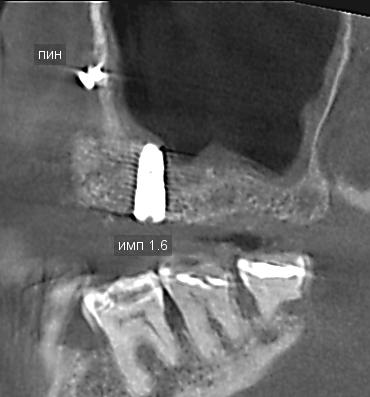

• Рентгеновские снимки, ортопантомограммы (ОПТГ), компьютерные томограммы (КТ), прицельные снимки до, во время и после лечения.

2. Рентгенологические исследования: Все доступные рентгеновские снимки (прицельные, панорамные, КТ-снимки) в динамике, выполненные в течение всего периода лечения и после него. Желательно предоставить как распечатанные варианты, так и цифровые копии на диске.